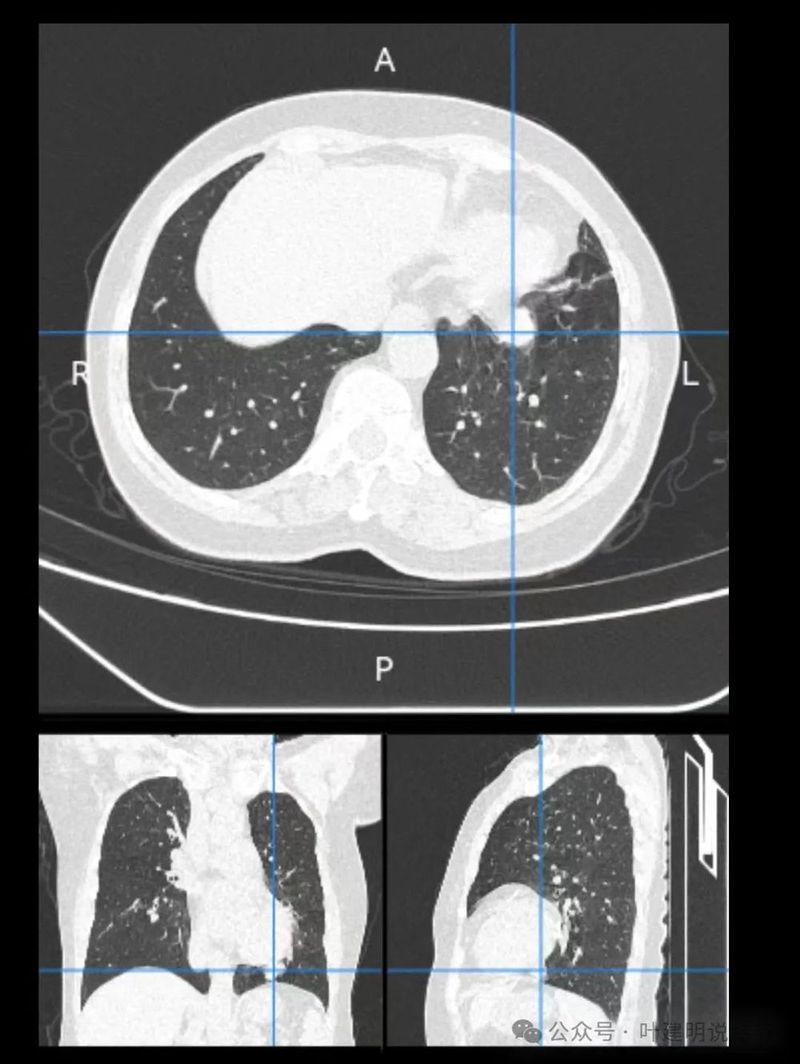

影像展示与分析:

先来看两肺多发病灶的情况:

再看左下主病灶连续层面与重建影像:

冠状位见病灶与周围结构有间隙,说明不像炎性,如果是炎症,挨这么近,一般会搭牢的。

矢状位病灶膨胀感不如横断们与冠状位明显,但东西是实性的。